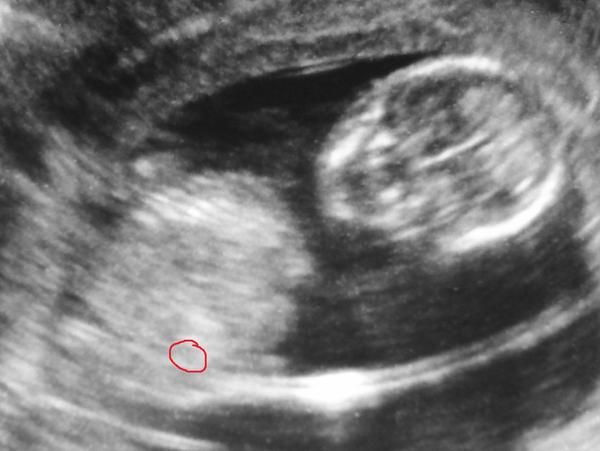

holky , tak jsem asi mela pravdu -- pokud výběžek, ze kterého bude casem pohlavni organ miri nahoru, bude to kluk, pokud dopředu, bude to holka. tedy u nas to vyslo -- pridavam fotku, dle které jsem to odhadovala jiz ve 13. tydnu -- a tedy je ze screeningu -- jde o prurez miminkem nikoli o foto jen z boku. .

Tak jestli jsem někdy měla pochybnosti o pohlaví na UTZ snímku, tohle mě usvědčilo v tom, že doktorka se nemohla mýlit. 🙂

Uplne dole: http://www.baby2see.com/medical/ultrasound.html